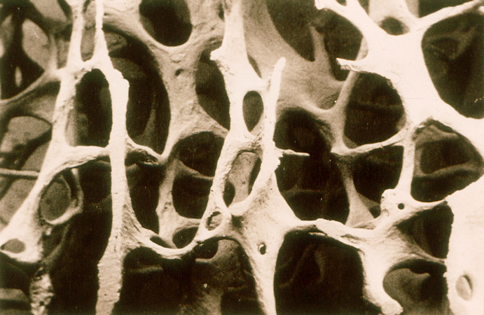

Остеопороз - хроническое заболевание с нарушением кальциевого обмена, поражающее костную ткань, при котором в ней образуются пустоты-поры, что влечет за собой чрезвычайную хрупкость костей, которые могут сломаться даже при небольших нагрузках.

При остеопорозе имеющаяся костная ткань разрушается гораздо быстрее, чем образуется новая. В итоге общая масса костного скелета уменьшается, кости становятся более хрупкими. Остеопороз чаще выявляется в шейных и грудных позвонках, костях верхних и нижних конечностей. Для болезни характерна деформация позвонков и нарастающая боль в спине при движении, частые переломы крупных и мелких костей. Больные даже иногда становятся меньше ростом на 10-15 см.

Нормальная кость

Остеопороз